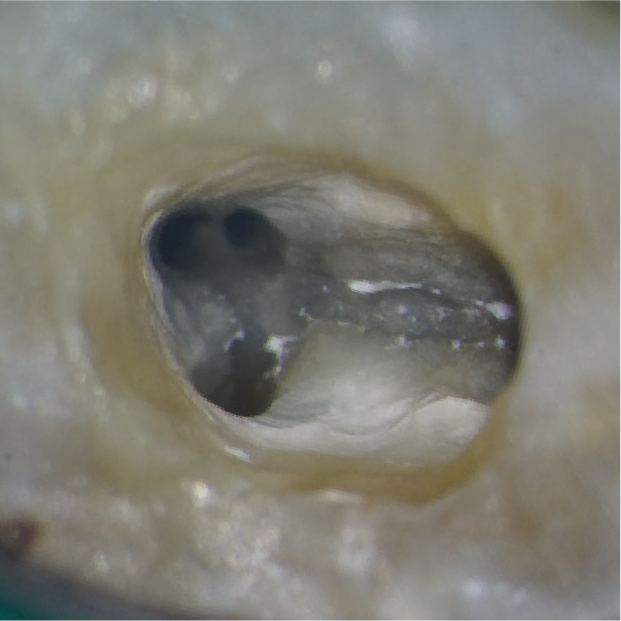

矢印の部分には、これまで見つかっていなかった細い根の管(根管)があります。マイクロスコープで大きく拡大して見ることで、わずかな入口を慎重に探し出し、丁寧に開くことができます。

その結果、隠れていた根管を安全に見つけ出し、適切な治療を行うことができました。